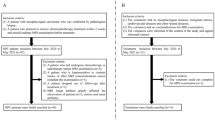

This study was approved by the medical ethics committee of our hospital, and the need for informed consent was waived due to the retrospective nature of this study. We retrospectively assessed 89 NPC patients whose diagnosis was confirmed by pathological examination of nasopharyngeal biopsy specimens from March 2017 to August 2021. The inclusion criteria included the following: patients who did not receive treatment for NPC before MRI scan and had no prior history of head and neck cancer; patients with diagnoses confirmed by pathological examination of biopsy tissues; patients with stage III–IVA NPC (staging based on the 8th Edition of the American Joint Committee on Cancer Staging System for NPC) [18] who received radiotherapy and concurrent cisplatin- or carboplatin-based chemotherapy and completed re-examinations when the prescribed dose reached 40 Gy and at one month after chemoradiotherapy completion. The exclusion criteria were as follows: lack of ASL images or no MRI examination; radiotherapy or chemotherapy before ASL MRI examination; patients with severe artifacts on ASL images or patients whose lesion region of interest (ROI) could not be outlined due to the small sizes of post-treatment tumor lesions. Finally, 55 patients were included for further image analysis (Fig. 1).

The tumor, node, metastasis staging of all patients was co-determined by two radiologists (J.L. and N.W., with 5 and 15 years of experience in head and neck radiology, respectively) based on the findings of head and neck MRI, thoracoabdominal computed tomography, MRI of other body areas, or nuclear medicine exams. The specific treatment regimens for NPC were as follows: a total prescribed dose of 70 Gy delivered to the primary nasopharyngeal lesions in 35 fractions (when calculated using a linear-quadratic formula [19, 20] [Eq. (1)], the total prescribed dose can be converted to a biologically effective dose [BED] of 84 Gy); 66 Gy (BED = 78.45 Gy) to metastatic lymph nodes, 60 Gy (BED = 70.29 Gy) for draining lymph nodes at high risk of containing cancer, and 54 Gy (BED = 62.33 Gy) for draining lymph nodes at low risk of containing cancer; five fractions weekly (one fraction each day) combined with concurrent cisplatin-based chemotherapies. All patients underwent three MR examinations before treatment initiation, when the prescribed dose reached 40 Gy to the primary nasopharyngeal lesions and at one month after chemoradiotherapy completion, with the MR regimen unchanged during the entire process. When the prescribed dose reached 40 Gy, all patients were divided into the partial response (PR) (36 cases) and stable disease (SD) (19 cases) groups based on the universal RECIST 1.1 standard [21]. At one month after chemoradiotherapy completion, the patients were re-divided into the residual (17 cases) and non-residual (38 cases) groups.

Fifty-five patients with locoregionally advanced NPC were finally enrolled in this study: 51 had non-keratinizing carcinoma (41 cases with undifferentiated carcinoma and 10 cases with differentiated carcinoma), and four had keratinizing squamous cell carcinoma. Forty-three patients were male and 12 were female, with a mean age of 55.76 ± 9.26 years. The staging data of the patients are shown in Table 1. Thirty-six patients were allocated to the PR group and 19 to the SD group. Re-examinations one month after chemoradiotherapy completion suggested that 17 patients had residual tumors and 38 did not, with significant differences in the percentage of residual tumor between the SD and PR groups (Table 2).